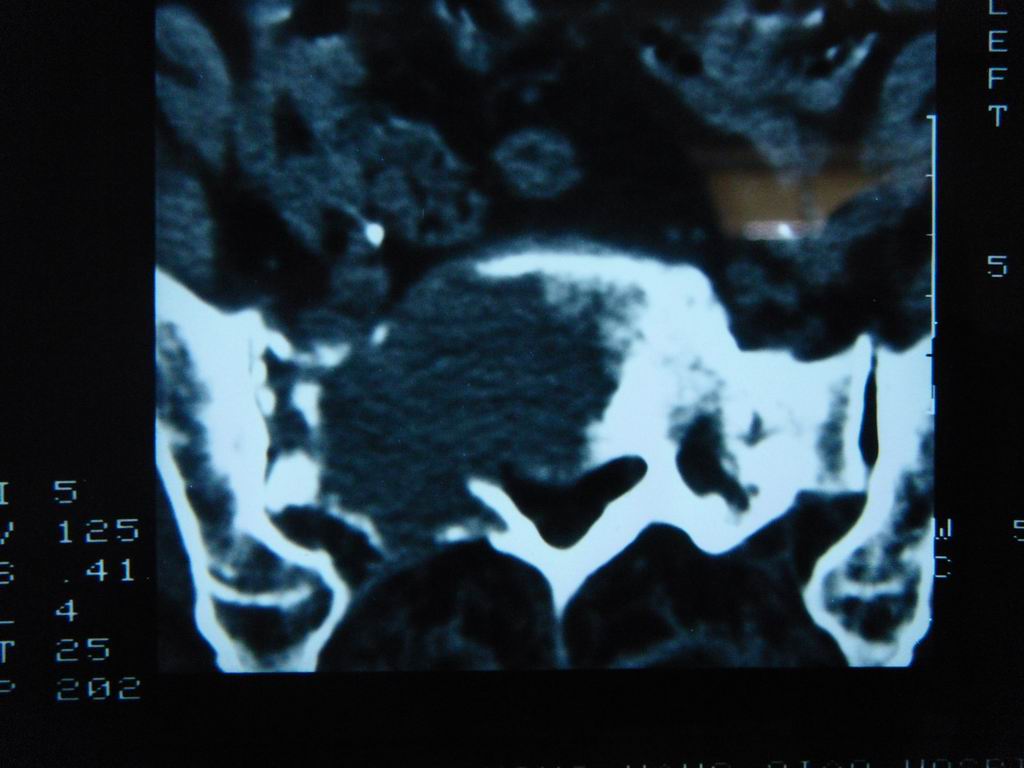

标题: CT21430:女性65岁 乳腺癌术后3年 [打印本页]

标题: CT21430:女性65岁 乳腺癌术后3年

结合病史,考虑骶骨转移瘤,但软组织肿块未突破骨壳,骨巨细胞瘤不能完全排除,骨髓瘤及脊索瘤不考虑。

结合病史,考虑骶骨转移瘤。

结合病史,考虑骶骨转移瘤。其它椎体,如腰5是否有问题呢?

个人感觉骨巨细胞瘤可能性大些。